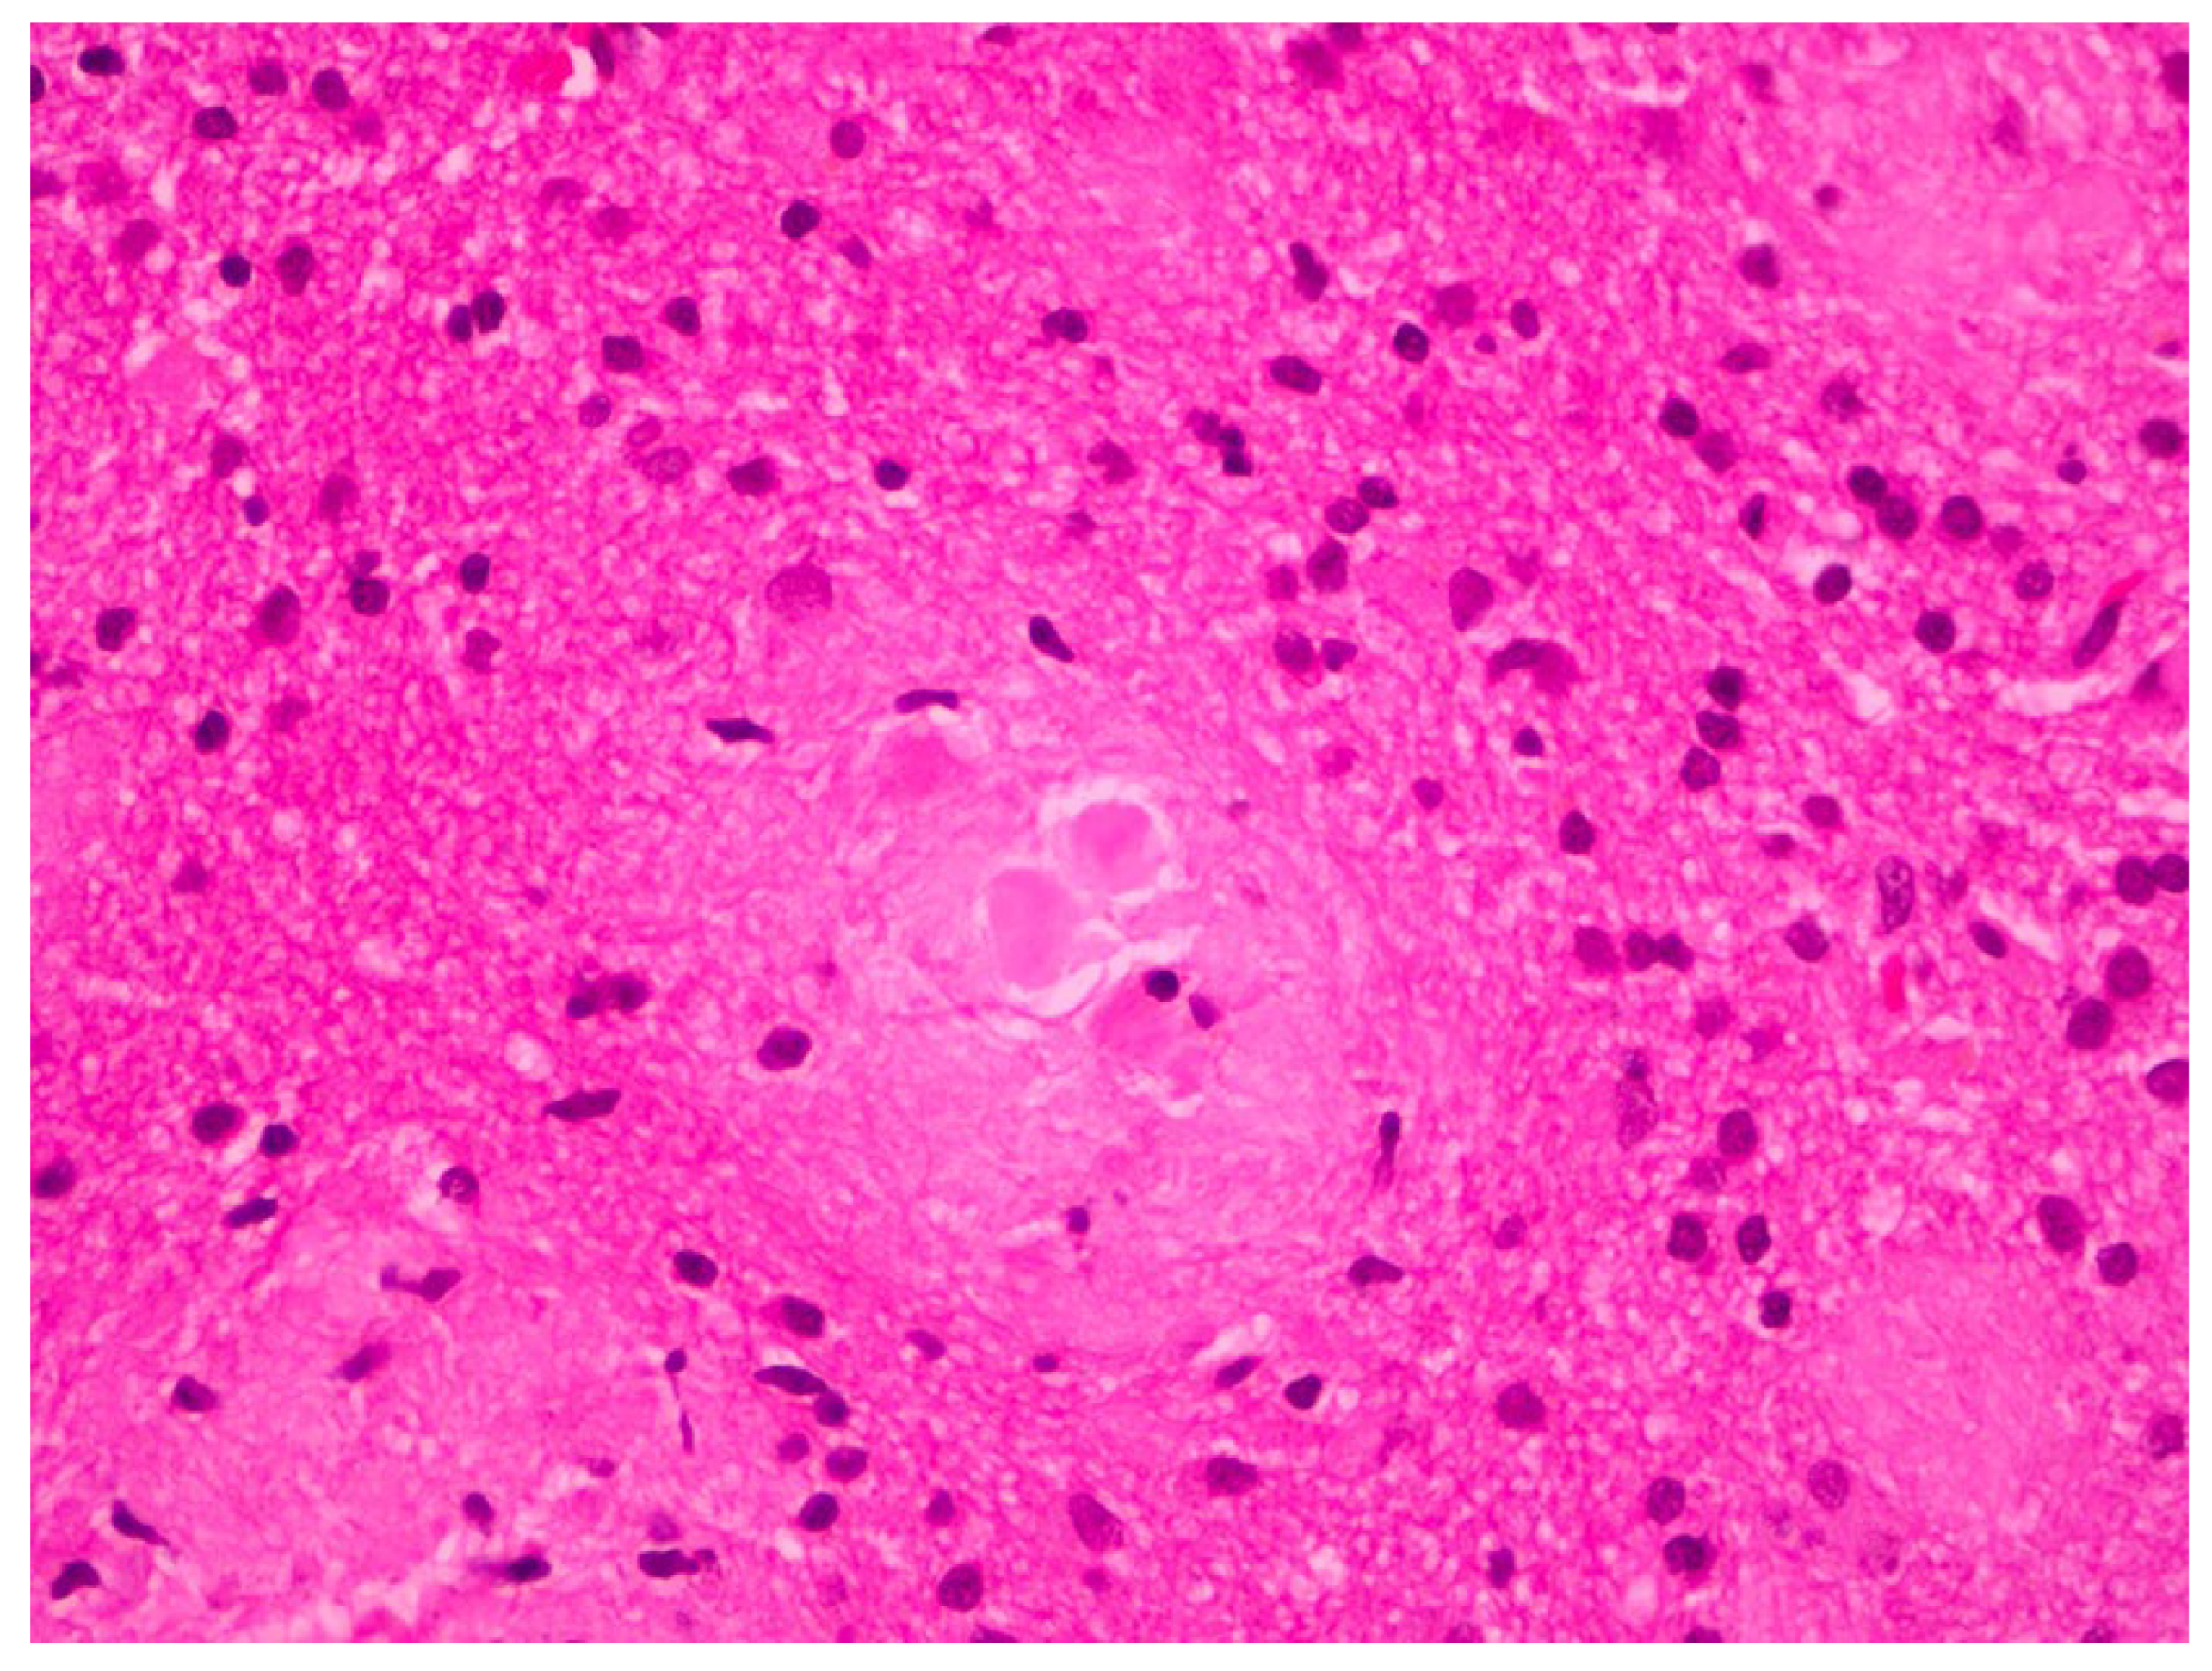

2. Case Report